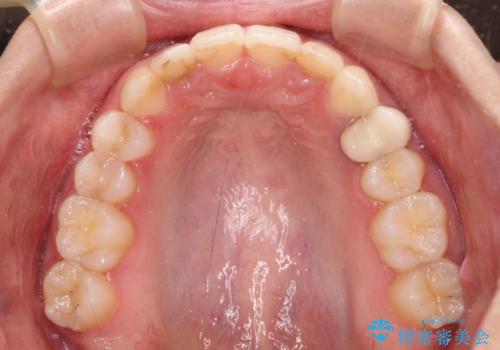

- 前歯の歯並びと神経を取って変色してしまった前歯を気にして来院された患者様です。

上下前歯の歯列不正はインビザラインにより整え、その後に、前歯2本をオールセラミッククラウンにて補綴治療することとしました。

下顎前歯が1本欠損しており、下顎歯列の大きさが本来よりも小さいため、上顎歯列とのバランスが悪く、深い咬み合わせになっていました。

上顎にIPRを多用して歯列の大きさを小さくするよう試みましたが、理想的な咬み合わせまでには改善させることはできませんでした。